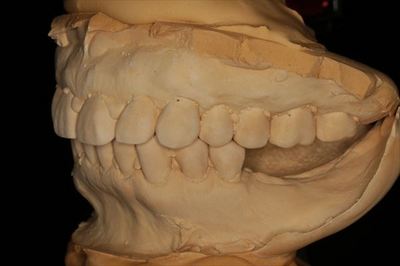

左上下歯列の現在の関係です。